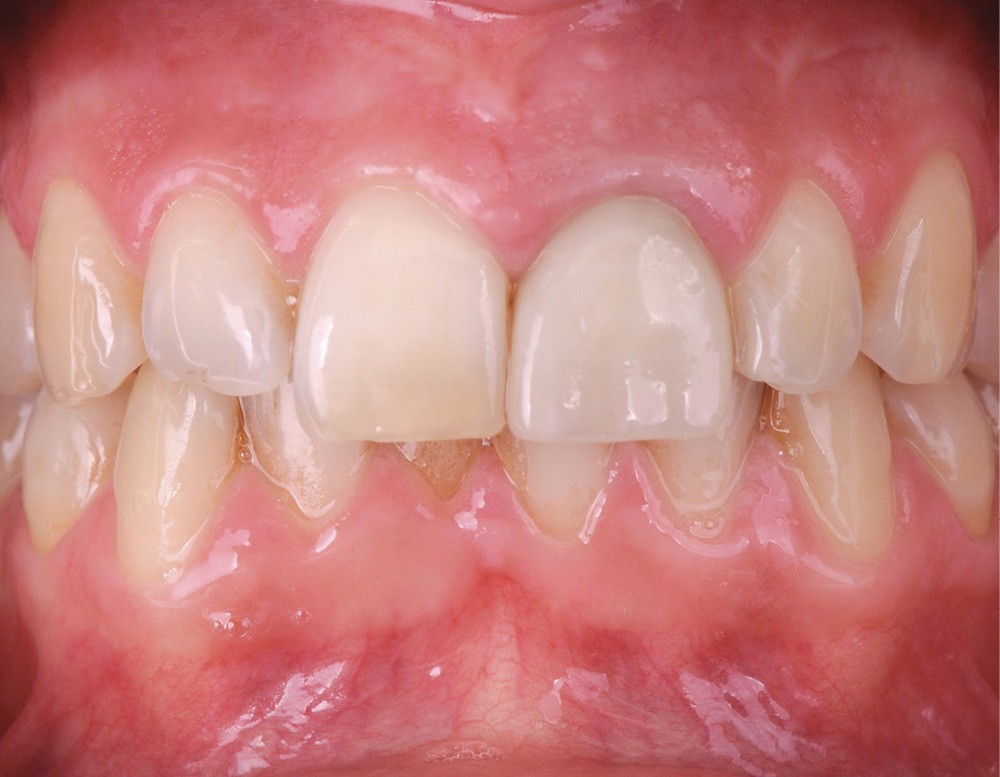

Une patiente de 32 ans est reçue en consultation au cabinet. Elle ne présente pas d’antécédents médicaux ou chirurgicaux. Elle se plaint de douleurs aiguës en regard de la 21 lors de la mastication. Cette dent a été traitée par son précédent chirurgien-dentiste il y a quinze ans, à la suite d’un accident de vélo. Un traitement endodontique a été rendue nécessaire ainsi que la pose d’un ancrage radiculaire de type inlay-core et d’une couronne céramo-métallique (fig. 1).

L’examen clinique révèle la présence d’un biotype parodontal épais, une gêne lors de la palpation vestibulaire ainsi qu’une douleur à la percussion. La réalisation d’une radiographie rétro-alvéolaire et d’un CBCT confirme la présence d’une fissure radiculaire (fig. 2).

Il est expliqué à la patiente la nécessité d’extraire la dent, au vu de la situation clinique, et la possibilité de poser un implant lors de cette même séance (la patiente ne présentant aucune contre-indication à l’implantologie). Il lui est également précisé qu’une couronne provisoire peut être réalisée le jour même.

En raison de ses exigences esthétiques et compte tenu du caractère d’urgence, la patiente accepte la proposition. Une prise d’empreinte numérique est réalisée avec une caméra optique.